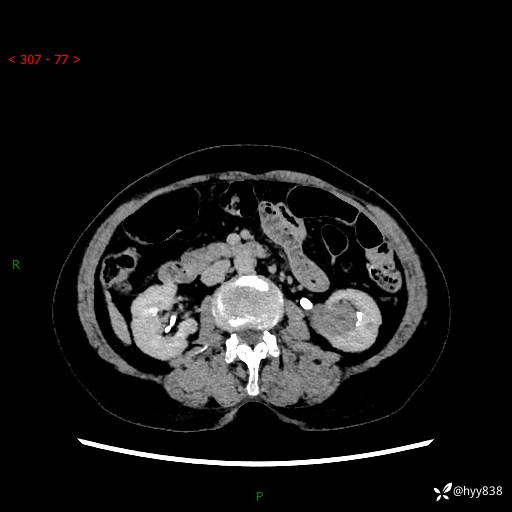

72岁/女,检查发现左肾占位1天。为了满足诊断,常规四期后,又加了延迟期-结果公布~

【患者信息】:72岁/女

【主诉】:检查发现左肾占位1天

【现病史及既往史】:患者于1天前检查发现左肾占位,无畏寒发热,无咳嗽咳痰,无腰腹部疼痛不适,无肉眼血尿、无尿频尿急症状,起病来,患者未行特殊治疗,为求进一步诊治,门诊以"左肾占位"收治入院。 发病来患者精神、饮食、睡眠良好,小便如上,大便正常,体重无明显变化。

【检查】:肾脏CT平扫+增强